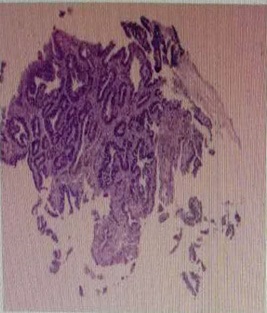

Figure 1: CT results of upper abdomen.

The patient, a 55-year-old male, was admitted to the hospital on March 11, 2021 due to “upper abdominal distension, pain and discomfort for more than 1 year, and recurrence for more than 2 months”. More than 1 year ago, the patient had no obvious inducement of upper abdominal distension, pain and discomfort, no acid reflux, heartburn, no nausea, vomiting, no hemesis, melena, no chest pain, chest tightness and other discomfort, no care, no diagnosis and treatment. Before 2 months, the patient’s symptoms were aggravated again, and the symptoms continued to be not relieved, so the emergency department was admitted to our hospital as “abdominal distension cause check”. Previous healthy, smoking and drinking history, no similar patients in the family. Improve relevant examinations after admission, such as: Infectious disease screening: hepatitis B surface antigen (gold standard method) positive (+), HBVDNA: 3.89 x 106 IU/ml, TAP: 128.03 um², liver function:TP: 50.23 g/L ALB: 27.8 g/L, TBIL: 34.8 g/L, DBIL: 15.00 g/L, IBIL: 19.8 g/L, ALT: 27 g/L, AST: 51 g/L, PCHE: 1879 g/L, AFP: 203.8 ng/ml, Color Doppler ultrasonography of chest and abdomen showed that liver cirrhosis was possible, portal vein velocity decreased, liver disease gallbladder, splenomegaly and splenic vein dilation. 256 row chest and upper abdomen CT (plain scan + enhanced): 1. Ground glass shadow of left lung, follow-up and reexamination are recommended; 2. Liver cirrhosis, splenomegaly, esophagogastric fundus and splenic collateral circulation; The abnormal enhancement focus in the right lobe of the liver, considering the high possibility of liver cancer, the remaining small nodule like enhancement in the liver, considering intrahepatic metastasis (Figure 1). 3. Gastric antrum space occupying, considering malignancy, please combine clinical and pathological findings. 3.0 Mr upper abdomen (plain scan + enhancement): 1. Liver cirrhosis with regenerative nodules, splenomegaly, portal hypertension, ascites and collateral circulation; 2. Abnormal signal of right posterior lobe of liver (Figure 2). Considering malignancy, please combine clinical and AFP examination. Gastroscopy showed: 1. Esophageal gastric fundus varices (severe); 2. Gastric antrum space occupying: Ca? (Figure 3); Gastric antrum pathology (HE staining Figure 4) results: (gastric antrum) adenocarcinoma. Liver puncture pathology (immunohistochemical (Figure 5) diagnosis: (liver puncture) combined with immunohistochemical results, it is consistent with hepatocellular carcinoma. Immunohistochemistry: CerbB2 (0), CK (+), HEPA (partial +), glypican (+), CD (small amount +), CD34 (blood sinus +), CK7 (-), CK8 (+), CK19 (-), CDX2 (-), Ki67 (50% +), GS (+), CK20 (-). Physical examination: Body temperature was 37OC, pulse was 78 beats/ min, respiration was 20 beats/min, blood pressure was 120/70 MHg, skin and mucosa of the whole body were mildly yellow, no rash, bleeding spots, liver palm or spider nevus, superficial lymph nodes were not touched and enlarged, and no obvious abnormalities were found in head, neck, heart and lungs during physical examination. Abdominal distention, soft abdomen, no obvious tenderness, rebound pain and muscle tension in the abdomen, liver, spleen and ribs are not touched, negative mobility dullness, bowel sounds are normal. The patient refused interventional therapy, asked for oral chemotherapy and was discharged after her symptoms improved.